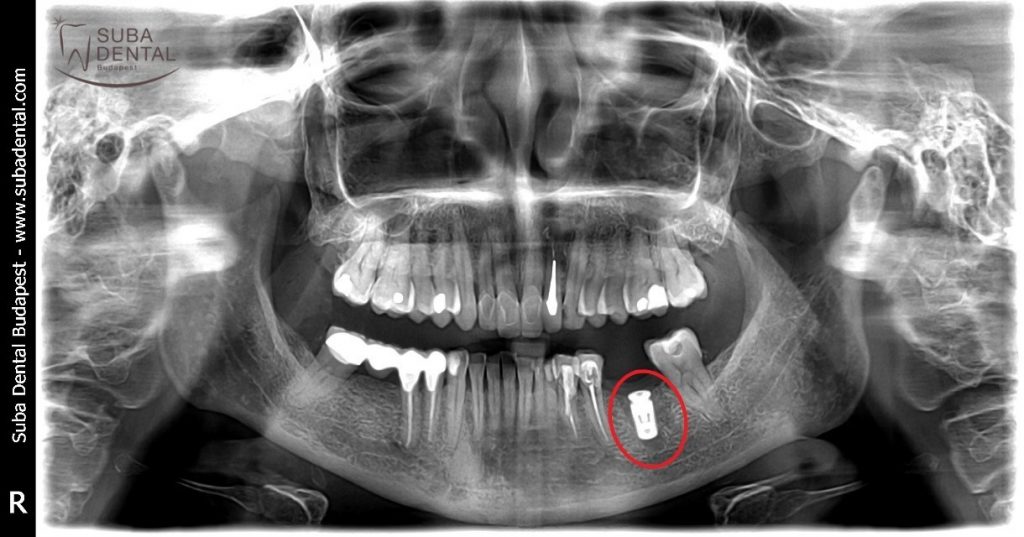

Sur la base de l'examen oral et de la radio panoramique réalisée dans notre clinique, un foyer dentaire a été diagnostiqué. En raison de l'inflammation (parodontite périapicale chronique) sur l’apex d’une dent préalablement dévitalisée et couronnée nous avons conseillé l’extraction de la dent.

L’inflammation autour de la racine de la dent 36 est bien visible sur la radio panoramique effectuée le 9 juin 2017